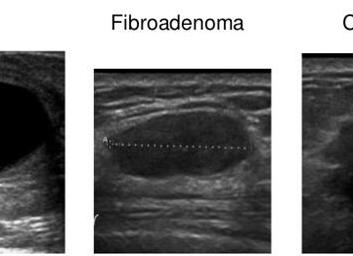

Фиброаденома на узи молочной железы

• УЗИ молочных желез. Наиболее информативно выполнять у женщин репродуктивного возраста — до 45-50 лет. Позволяет дифференцировать новообразование и дает представление о тех зонах и тканях, которые невозможно увидеть при рентгенологическом исследовании. Но не отражает характер у опухоли — злокачественный или доброкачественный.

В диагностике особое значение имеет самостоятельный осмотр молочных желез, при пальпации которых определяется четко ограниченная смещаемая опухоль. Наличие узлов так же может определить врач-специалист, после чего женщине назначается УЗИ молочной железы или маммография для более точной визуализации поражения. Главное отличие фиброаденомы от рака молочной железы — это смещаемость опухоли и четкие контуры при физикальном обследовании и УЗИ.

Как правило для установления диагноза достаточно осмотра хирурга-онколога, УЗИ молочной железы и пункционной биопсии. В некоторых случаях требуется выполнение маммографии.

1. УЗИ. Исследование рассмотреть структуру опухоли, ее размеры и локализацию.